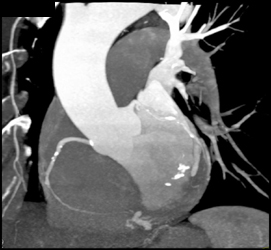

Diagnosis

Stent in LAD